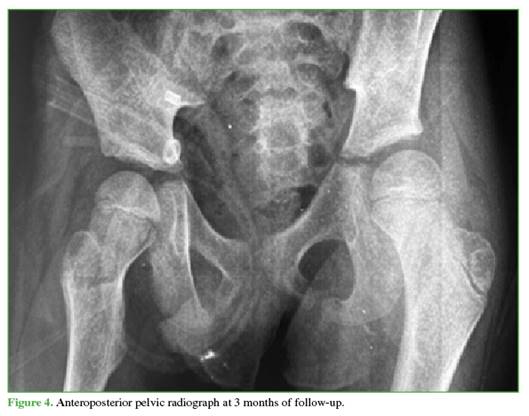

Follow-up radiographs at 3 (Figure 4) and 6 months (Figure 5) showed no evidence of AVN, and other musculo-skeletal complications associated with traumatic dislocation were also ruled out.

Follow-up radiographs showed no signs suggestive of AVN (sclerosis, collapse, cysts, joint-space narrowing, etc.).22 These findings may take 2 to 6 months to become visible on radiographs,20 so the follow-up schedule was appropriate.

Despite the absence of radiological signs of AVN up to 6 months, continued imaging follow-up is necessary to detect potential development of AVN, which may take up to 2 years to manifest.25